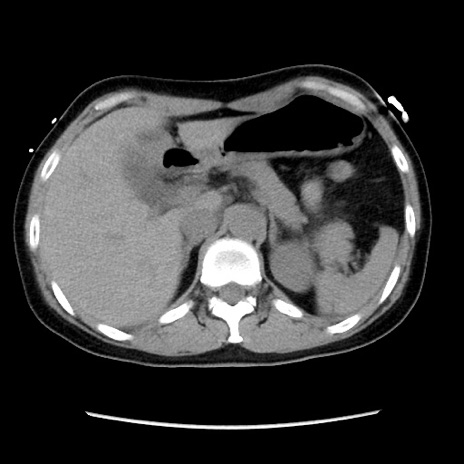

矢状断像

【症例】 50歳代女性

【主訴】 腹痛

【現病歴】前日生レバーを食べた。今朝に排便あり。 昼前に突然発症の腹痛を生じ、当院救急外来を受診した。

【既往歴】 子宮筋腫にてで子宮全摘後

【身体所見】 意識清明、腹部:平坦、軟、下腹部やや左を中心に圧痛・反跳痛あり、筋性防御あり

【データ】WBC 7800、CRP 0.07